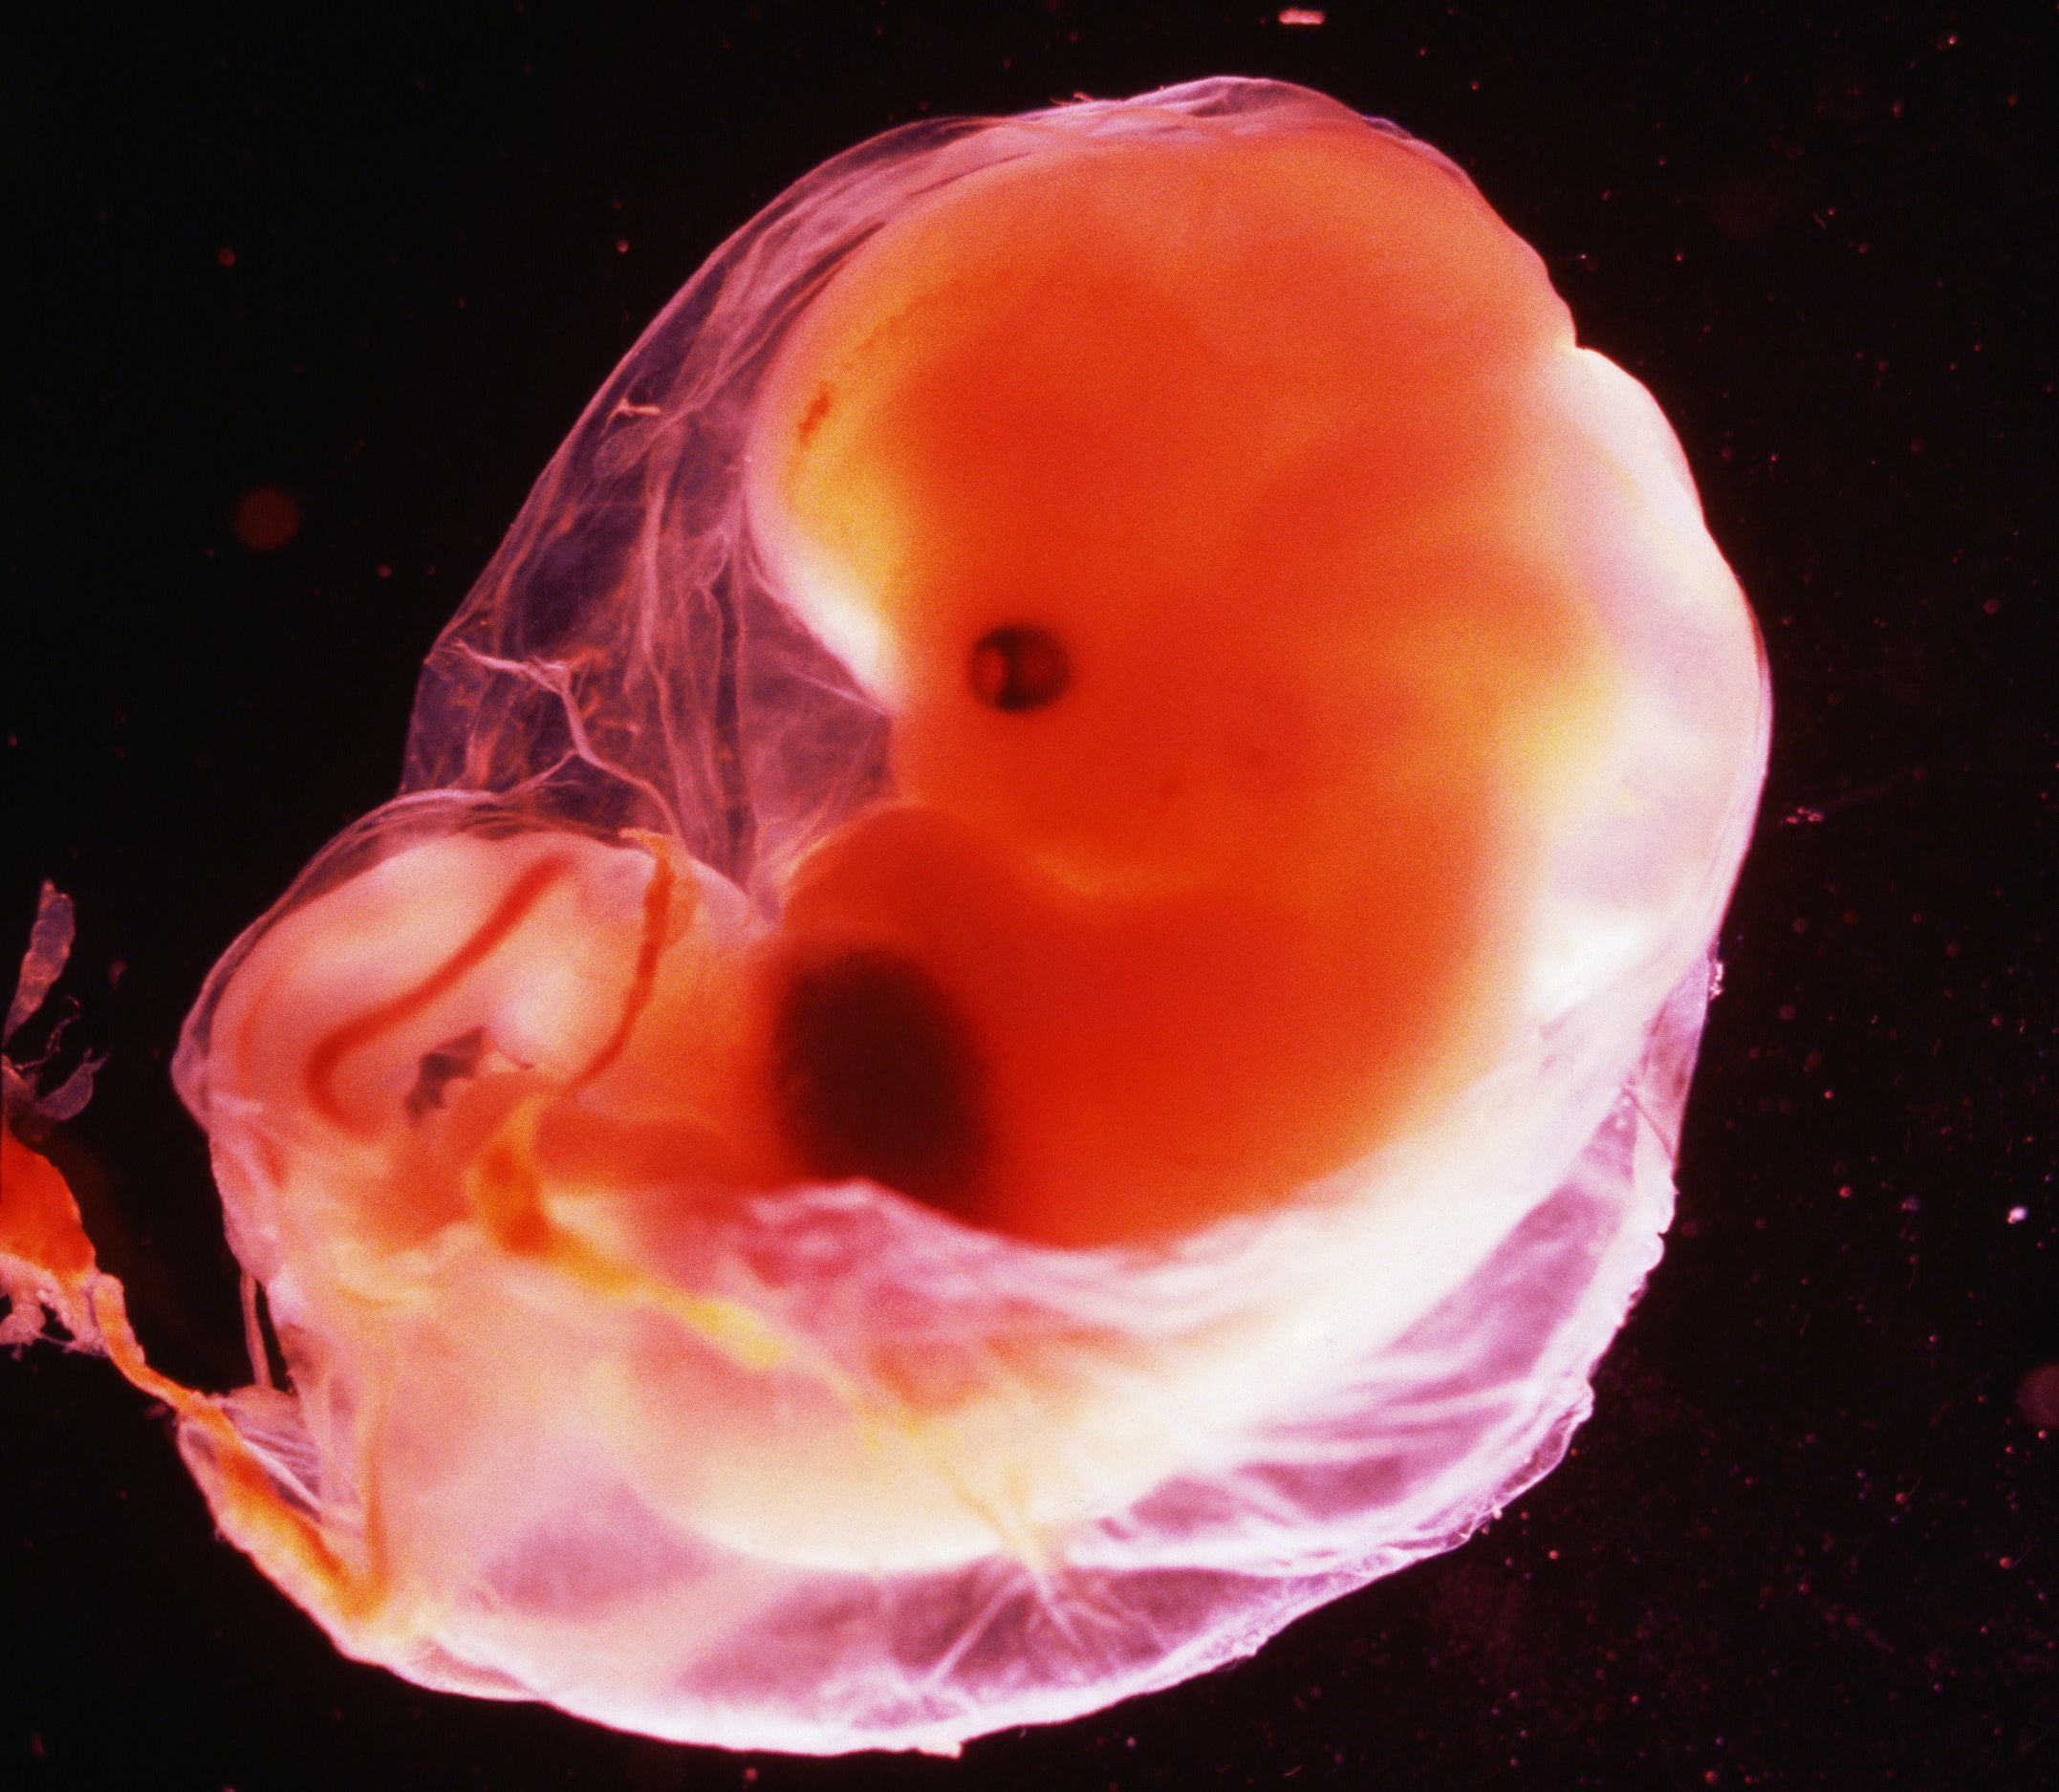

Зарождение жизни: Фотографии Леннарта Нильсона